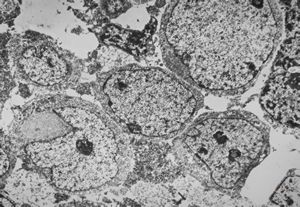

M, 70y. | mycosis fungoides - Sézary cell

M, 70y. | mycosis fungoides - Sézary cell